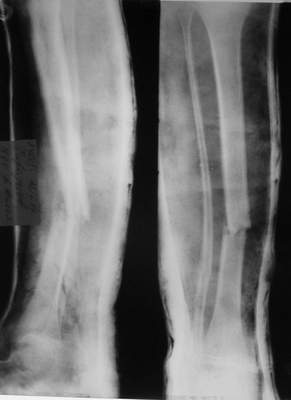

A>> Перелом костей н\3 правой голени со смещением.

Есть даже тень периостальной костной мозоли и сросшийся перелом

малоберцовой кости.

Это сросшийся перелом малоберцовой кости. И ложный сустав

н\3 б\берцовой кости.

Так как речь зашла непосредственно о травме, см этапные

снимки. Как все было

Первичные